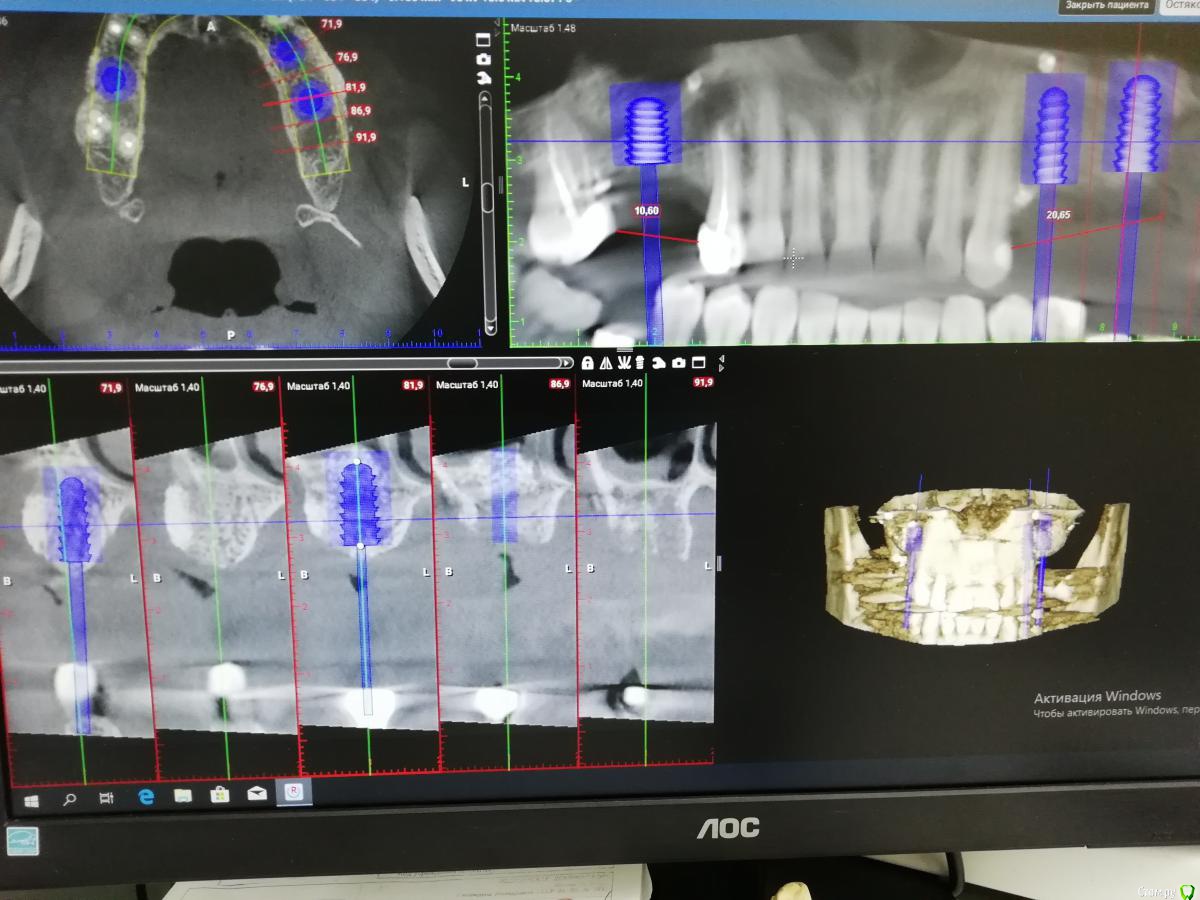

___49___ Опубликовано 23 декабря, 2019 Автор Поделиться Опубликовано 23 декабря, 2019 Планирую Импланты:обл16 - 6х8 обл 24- 4.5х12обл 26- 6х12 Коментарии, критика , свое виденье планирования уважаемые коллеги высказывайте. Спасибо . Ссылка на комментарий

___49___ Опубликовано 23 декабря, 2019 Автор Поделиться Опубликовано 23 декабря, 2019 Сам из косяков вижу - не достаточную отслойку шнайдера в области 26го ближе к носовому ходу. Ссылка на комментарий